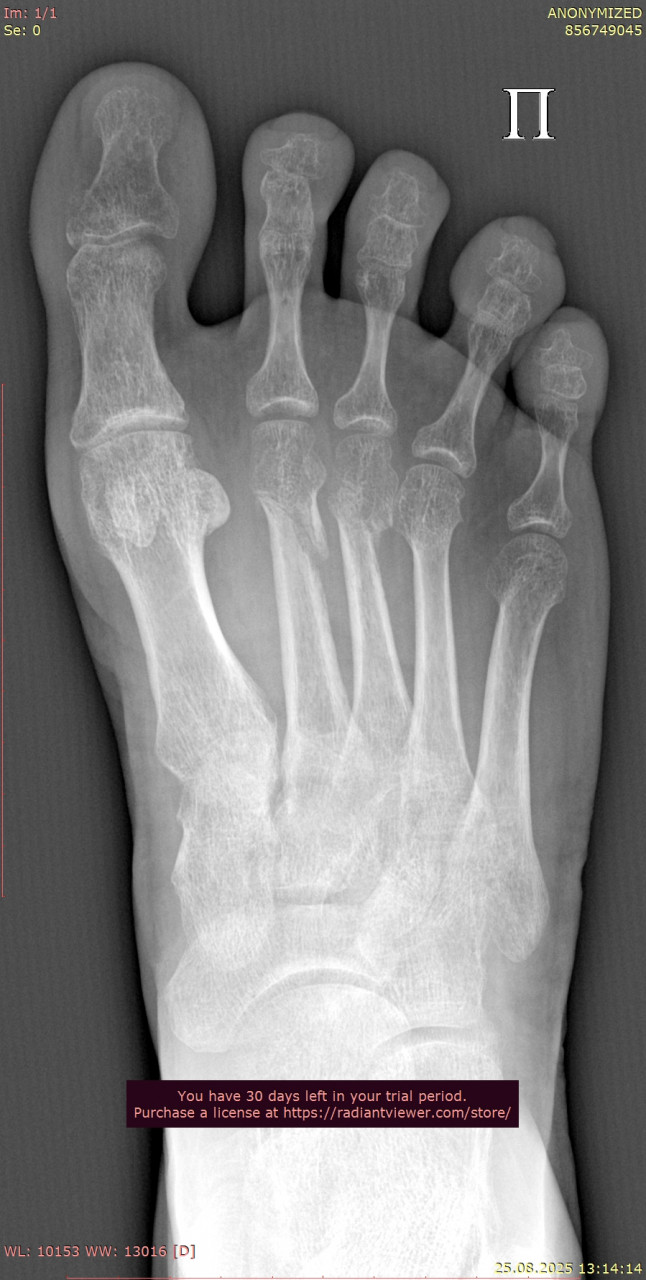

Сравнивая ваши снимки от 23.06 и 25.08:

- Линии переломов на костях стопы и области голеностопного сустава больше не прослеживаются чётко, видна формирующаяся костная мозоль – это признак заживления.

- Смещения отломков нет, контуры выровнены, что говорит о правильном срастании.

- Для срока 2 месяца после перелома динамика положительная, основные признаки консолидации присутствуют. Обычно к этому времени разрешают постепенную нагрузку, но полное снятие опоры (ходьба без костылей, тростей) должно быть постепенным и согласовано с вашим травматологом.

По поводу артроза, на рентгене действительно заметны начальные изменения в суставах стопы (сужение суставных щелей, небольшие краевые разрастания), но они умеренные и для 38 лет не критичны. Такие изменения часто встречаются после травм и нагрузок, но выраженного деформирующего артроза нет.

По вашим новым снимкам от 28.07 и контрольным от 25.08 признаков несращения или смещения нет т.к переломы в области стопы и голеностопного сустава консолидируются, костная мозоль выражена, контуры ровные. То есть прочность костей уже достаточна, чтобы постепенно начинать ходьбу без ходунков. То, что вы пока ставите ногу без активного сгибания пальцев, допустимо и так обычно и бывает на этапе ранней нагрузки. Постепенно с помощью ЛФК и разминки подвижность пальцев и стопы восстановится. Перегрузки голеностопа при аккуратной ходьбе на полной стопе сейчас не будет, наоборот  умеренная нагрузка нужна для правильного ремоделирования костной ткани.